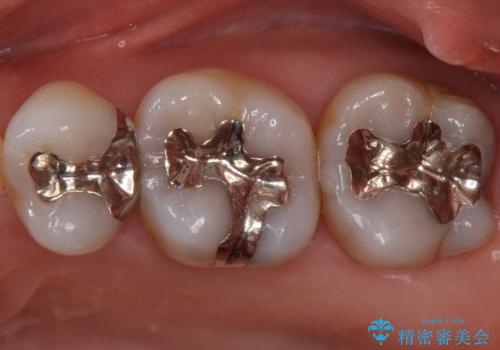

銀歯を白くしたい セラミックインレーでのやり替え

- 銀歯を白くしたいとのことで来院されました。

特に大きな虫歯もなかったため、周りの歯を残しつつセラミックインレーでの修復処置をしていきます。

- 左上567 セラミックインレー:77,000円×3本費用は治療当時の料金となります